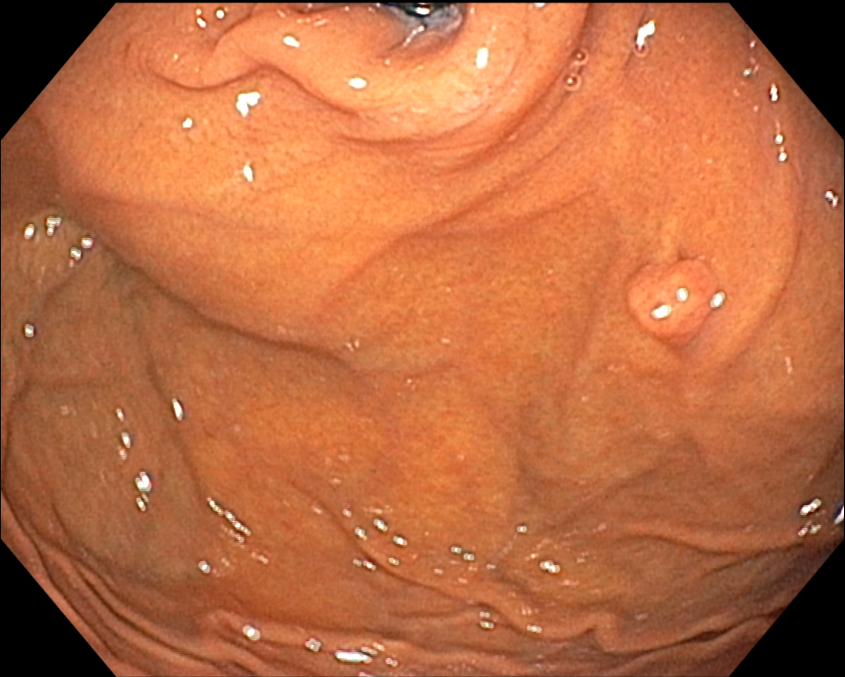

Fundic gland polyp, malignant potential and management

D Fundic gland polyp이고 제거할 필요가 없습니다.

Fundic gland polyp의 악성 잠재성 (malignant potential)은 없습니다. Somatic APC gene mutations이 dysplasia가 없는 syndromic fundic gland polyps의 70 % 이상에서 발견되었으나 sporadic lesions에서는 10 % 미만이었습니다. Sporadic fundic gland polyps과 PPI와 관련된 polyps은 실질적으로 악성 잠재성이 없습니다. 그러나 dysplasia가 드물게 있기도 합니다. FAP 환자의 fundic gland polyps의 경우 30-50%는 dysplasia를 나타내지만 전형적으로는 low grade입니다. 그러나 FAP 환자에서의 adenoma와 대조적으로 fundic gland polyps은 거의 암으로 진행하지 않습니다. Fundic gland polyps은 빈번하게 다발성이고 한 개 이상 대표적인 몇 개의 조직검사로 충분합니다. 남은 polyps은 내시경으로 주의 깊게 (?) 관찰하고 다른 곳과 달라 보이는 polyps은 조직검사를 하고 가능하면 제거합니다. 1 cm 이상의 polyps, 궤양이 있는 poylps, antrum에 있는 polyps은 절제해서 dysplasia는 없는지 neplasia는 없는지 확인해야 합니다. |

Familial polyposis syndrome 가능성은 poyps이 20개 이상인 경우, antrum에 fundic gland polyps이 있는 경우, 젊은 나이 (40세 이전)에 발생한 fundic polyps, 십이지장에 adenoma가 동반된 경우에 고려되어야 하고 대장내시경을 시행해야 합니다. PPI 사용으로 여겨지는 sporadic fundic gland polyps 환자에서 polyps이 20개 이상이거나 1cm보다 큰 경우에는 PPI를 중단합니다. 이와 같은 환자에서 hypergastrinemia는 gastrinoma (Zollinger-Ellison syndrome) 또는 좀 더 일반적으로는 PPI-induced hypochlorhydria를 시사하고 존재한다면 PPI 용량을 줄이거나 중단합니다. 만일 GERD 치료를 위해 위산 분비 억제가 필요하고 H2R blocker로 치료되지 않으면 가장 낮은 용량으로 다른 PPI를 고려합니다. |